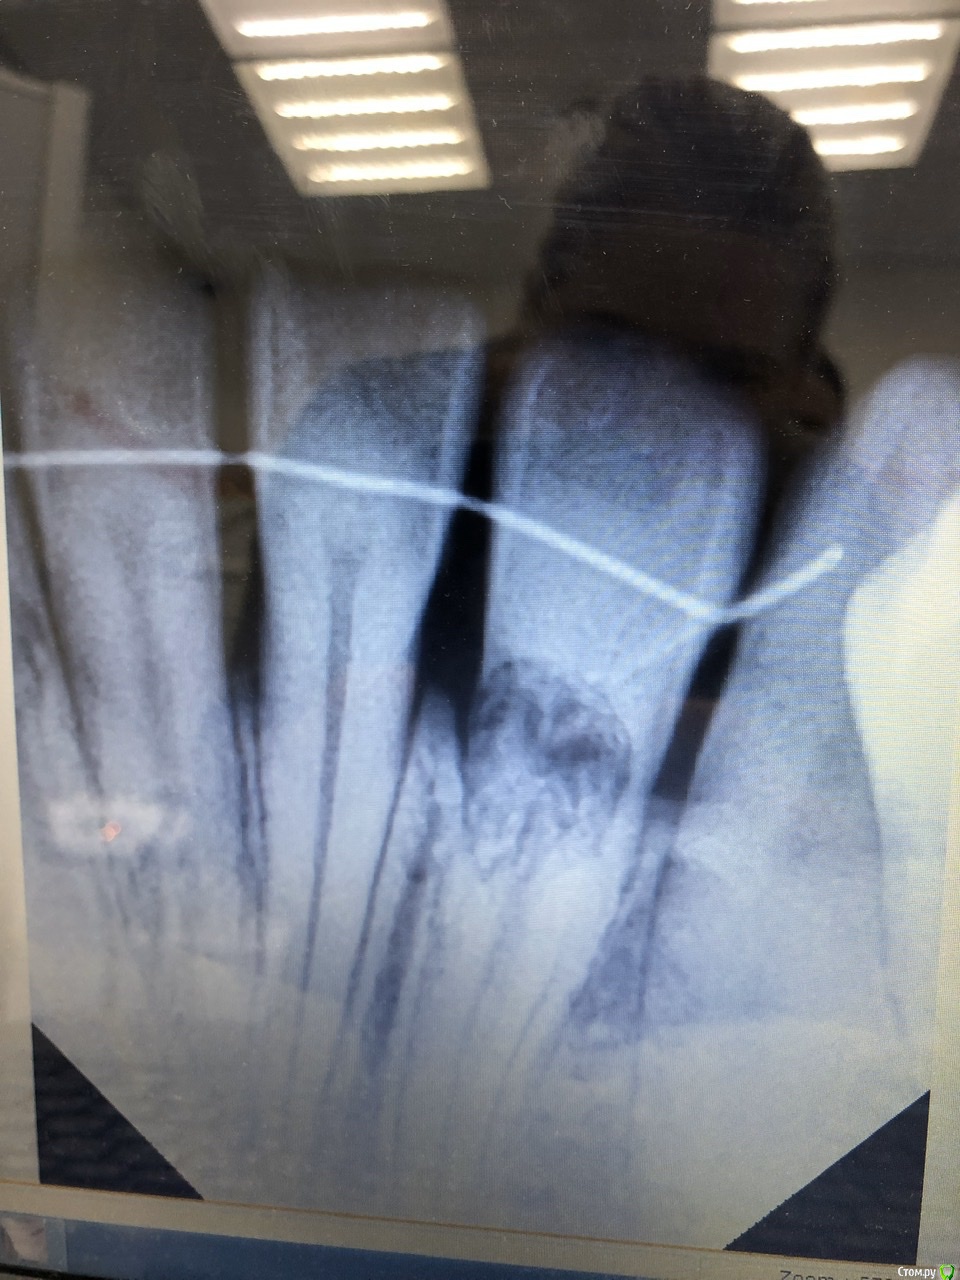

В июне 2019 года обнаружилась цервикальная резорбция двух нижних двоек. Полгода ушло на поиски врачей, вроде нашла, но сейчас немного сомнении, есть ли у нас шансы? Была в клиниках двадцати, две взялись именно лечить, выбрала ту, где было более внимательное и детальное обследование.

Ранее, в октябре 2017 обнаружена корневая резорбция нескольких передних верхних зубов, долго обследовалась и консультировалась, в итоге их просто наблюдаем и установили ретейнеры. С 15 до 20 лет стояли брекеты, прикус неправильный и после лечения. Сейчас 33 года.

Вопроса два - есть ли шансы остаться со своими нижними зубами и могла ли цервикальная резорбция быть вызвана полосками для отбеливания Crest?